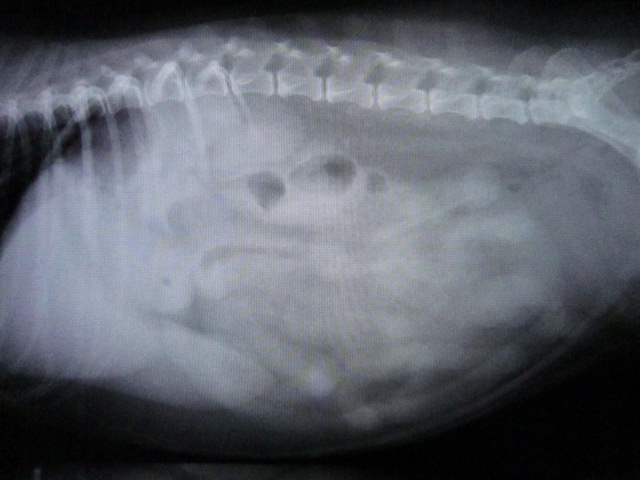

子宮蓄膿症

術中のレントゲンです。

肥大した子宮が出てきました。

摘出後、穿刺してみると中に膿がたまっていました。